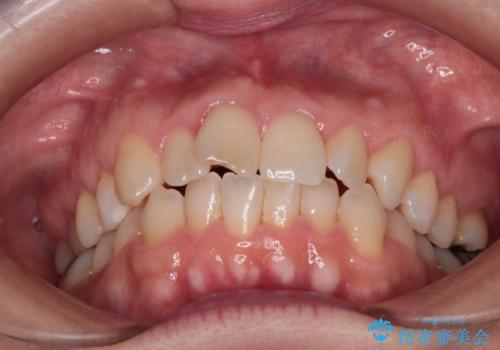

【インビザライン 】前歯のガタガタを治したい

- 前歯のガタガタを主訴に来院されました。

インビザライン で治療しました。途中は使用時間が20時間を切ることもありましたが、それでも頑張って使っていただき1年半で矯正終了することができました。